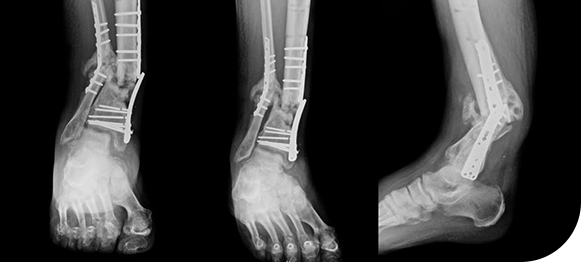

Fracture

Fracture care involves diagnosing and treating broken bones using both non-surgical and surgical techniques. Treatment plans are tailored to ensure proper alignment, healing, and a safe return to daily activities.

Nonunion

A nonunion occurs when a fractured bone fails to heal properly over time. Specialized orthopedic treatments are used to stimulate healing, restore bone stability, and prevent long-term pain or disability.